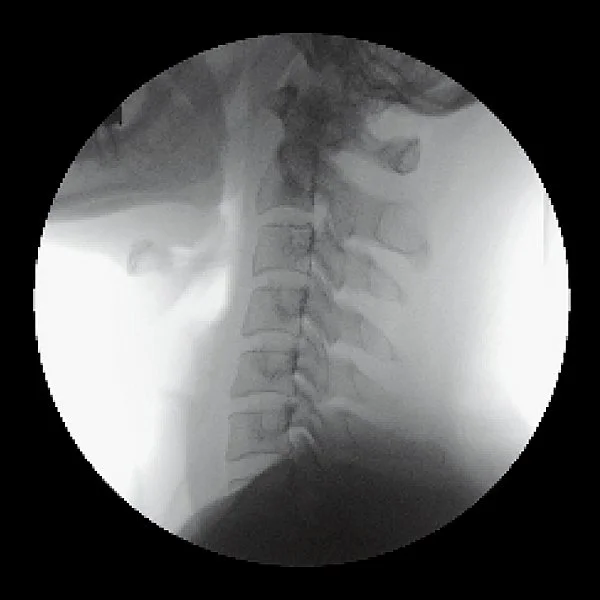

Take 2. Neck (C-spine) without RadSafe Filter

Take 2. Neck (C-spine) with RadSafe Filter